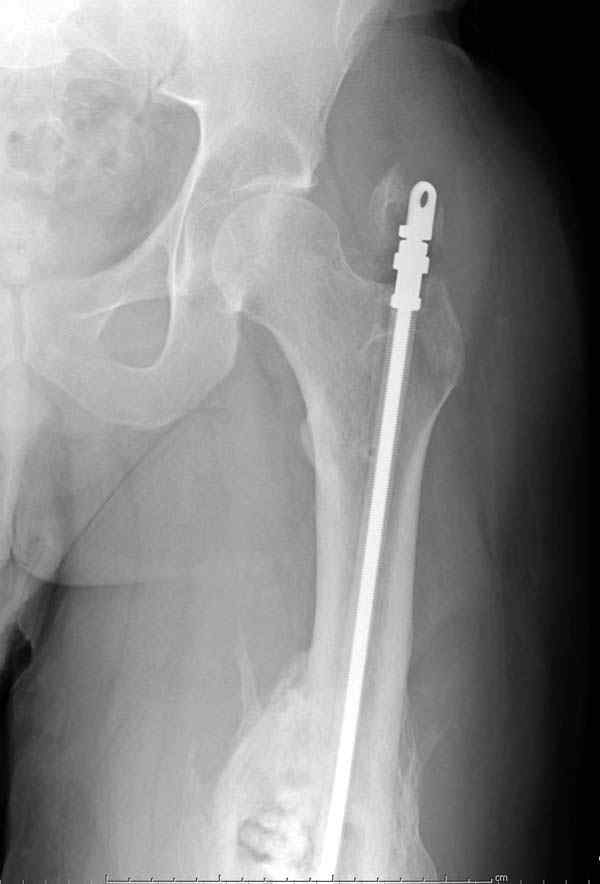

После нескольких некрэктомий, проведения аутодермопластики и заживдения ожоговой раны через 2 месяца после травмы произведен открытый остеосинтез левой бедренной кости штифтом и пластиной (деротационной) [image 01, 02]. Через 1 год и 7 месяцев после травмы у больного диагностированы ложный сустав и хронический остеомиелит левой бедренной кости. Произведено удаление металлических фиксаторов, секвестрэктомия и остеосинтез бедренной костивнешним двухплоскостным стержневым аппаратом [image 03, 04] .